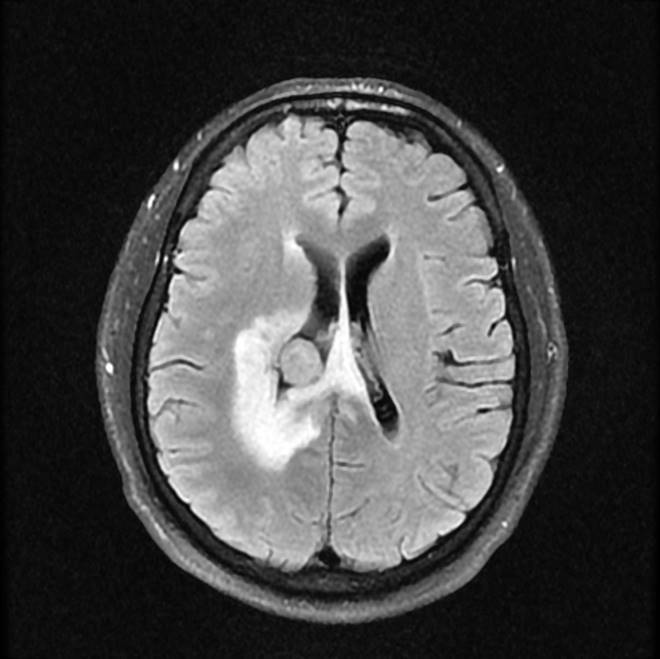

磁共振影像圖

圖3

MR診斷:右側(cè)側(cè)腦室三角區(qū)及側(cè)腦室旁占位,考慮惡性腫瘤可能,間變型腦膜瘤?轉(zhuǎn)移瘤?